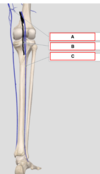

Identifiez A

Veine grande saphène

Identifiez C

Veine petite saphène

Identifiez B

Veine poplité